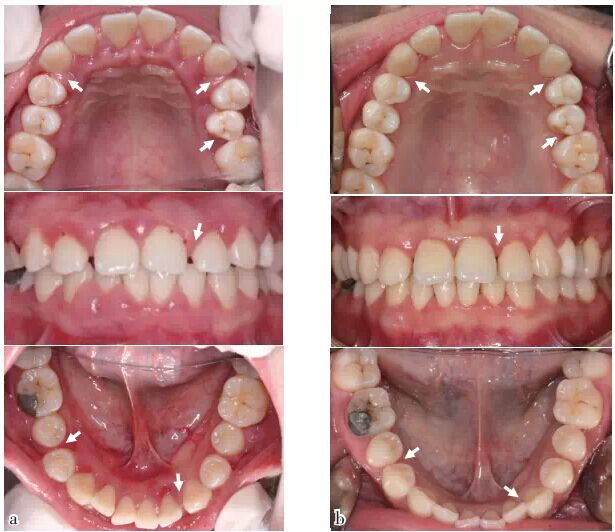

QQ圖片20150710154503.jpg

圖1 口內(nèi)照:與初診相比,SRP及咬合干預(yù)后,牙齦炎癥減輕,25排列整齊,多處牙間隙變小或關(guān)閉(箭頭),(a)2011/12初診,(b)2014/11評估